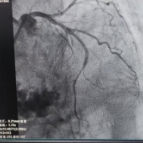

介入手术前

介入手术后

患者左爷爷,既往高血压病史多年,近期时常感阵发性心前区隐痛及憋闷,11月10日因胸痛10余小时就诊苗圃社区卫生服务中心(衡阳市第一人民医院胸痛单元),完善心电图检查提示急性前壁ST段抬高型心肌梗死,立即由120急救车转运至衡阳市第一人民医院。胸痛中心迅速启动胸痛救治流程,冠脉造影提示前降支中段狭窄99%,其远端TIMI血流1级,考虑患者超高龄,基础疾病多,出现恶性心律失常、心源性休克、心梗后机械并发症、泵功能衰竭、猝死等概率极高,同时予以充分抗栓后出血风险明显增加。经过紧密的术前讨论决定开通病变血管后予以药物球囊干预处理,术中患者出现了恶性室性心律失常、血压及心率急剧下降、球囊扩张后无复流等层层生死关卡。最终经充分扩张靶血管病变后于前降支中段行药物涂层球囊处理,复查造影显示前降支中段残余狭窄约30%,其远端TIMI血流恢复至3级,未见夹层、血管及冠脉破裂,术后患者安全返回ICU病房。